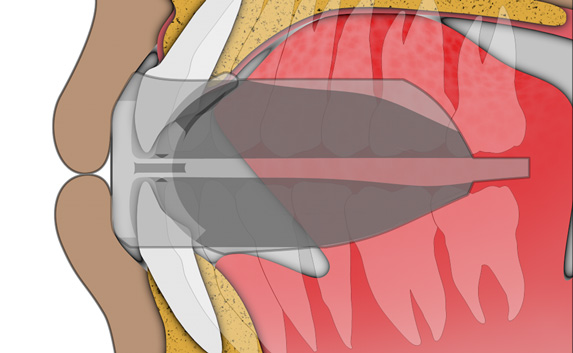

The TMJ Appliance®, which does not require any special fitting, is designed to act as an initial diagnostic and treatment tool for TMJ disorder. It works by decompressing the temporomandibular joint (TMJ), helps to correct mouth breathing and tongue posture habits, as well as limits bruxing. The TMJ Appliance® achieves TMJ disorder symptom relief immediately by alleviating pressure on the TMJ and relaxes the muscles around the jaw and neck.

The TMJ Appliance® treats both intracapsular and extracapsular disorders—TMJ clicking and pain (intracapsular) as well as pain referred from the craniomandibular muscles (extracapsular).